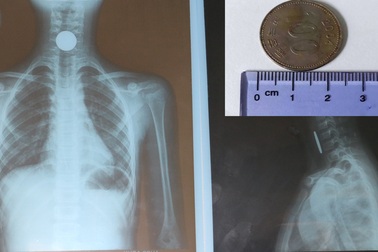

Gắp đồng xu có đường kính hơn 2cm từ thực quản bé gáiVừa ngậm đồng xu trong miệng, vừa trêu đùa với bạn, không may cháu Nguyễn Thị Q. N. (trú phường Kỳ Thịnh, thị xã Kỳ Anh, Hà Tĩnh) nuốt vào cổ. Sau khi được đưa vào bệnh viện, các bác sĩ tiến hành soi gắp thành công đồng xu có đường kính 2,3cm từ thực quản của cháu N.